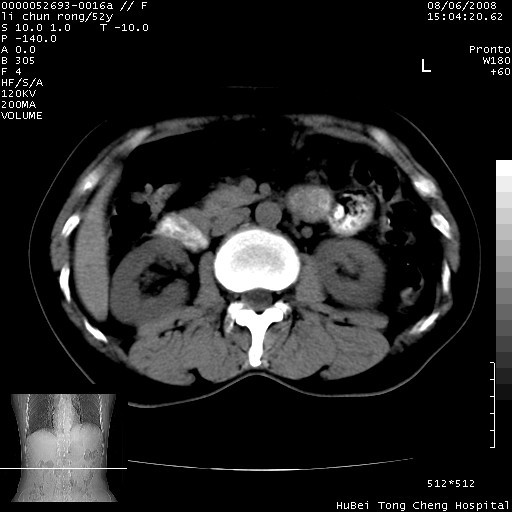

以下是引用云翔在2008-8-7 6:20:00的发言:[br]胰尾部囊性病变,考虑假囊肿,结合实验室检查疾病史

以下是引用zjzjr在2008-8-7 8:38:00的发言:[br]支持胰腺炎伴假囊肿形成,左肾小囊肿.少量腹水.

以下是引用随光逐影在2008-8-7 9:12:00的发言:[br]1)考虑胰腺炎伴假性囊肿形成可能性大;胰腺囊腺瘤待排。2)左肾小囊肿。3)少量腹水。